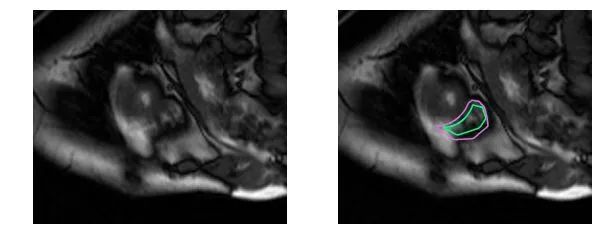

下面用几组图片来感受一下这种分割问题的困难。下图是右心室的MRI图片:

再困难一点:

而对于未训练过的肉眼,右心室区域是这样的: